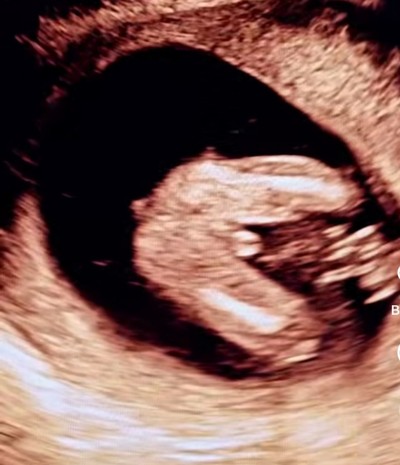

Cinsiyet tahmini yapabilirmisiniz

Gebelik haftası 20

Canım erkek demesi lazım çok belli oluyor

Doktor yalandan söylememiştir bu yüzde yüz erkek beli yani

Erkek bence canım benim de bu şekil ultrasonum var çıkıntı yok kızım olcak

Yüzde yüz erkek. Daha fazla erkek olamazdı :) Sağlıkla kucağınıza alın.

Erkek gibi duruyor kızlarda üç çizgi erkeklerde iki çizgi olurmuş doktor niye demedi ki bariz ortada aslında devletse 16 haftaya kadar söylemiyor cinsiyeti